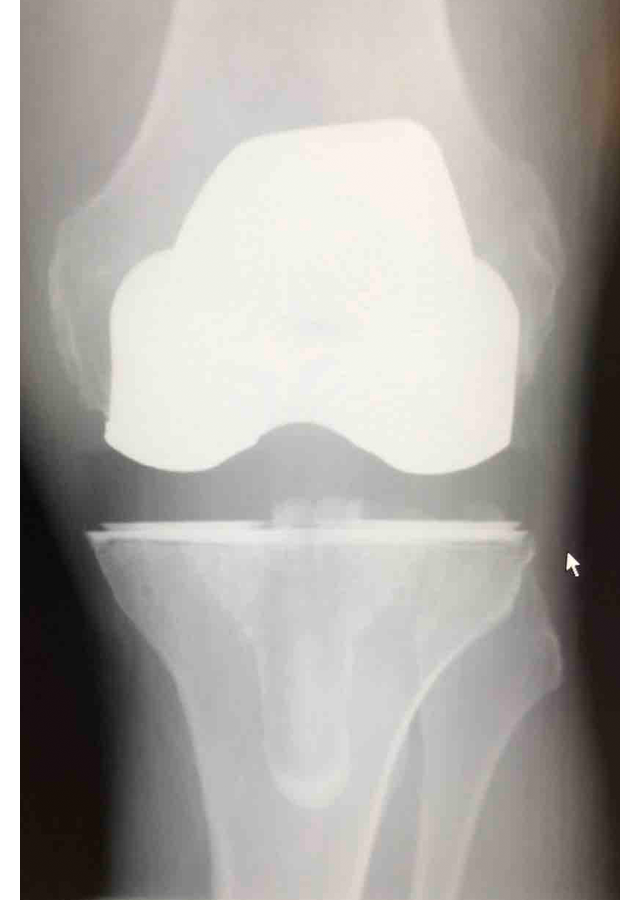

Csípő és térd ízületi betegségek protetizálása

Degeneratívtól, posttraumáson át veleszületett deformitásokig, revíziók, egyszerű és bonyolult helyzetek megoldása.